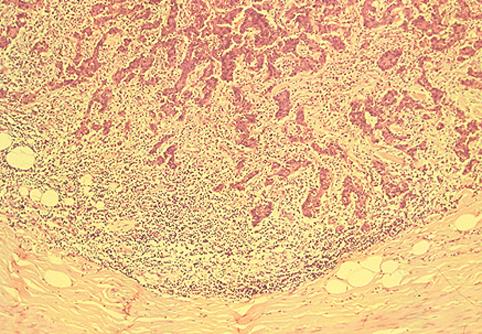

部位(臓器別)大腸/盲腸

検査方法ミクロ

腫瘍の肉眼分類0型(表在型)/その他

病変の最大径(ミリ)20〜24

腫瘍の深達度sm